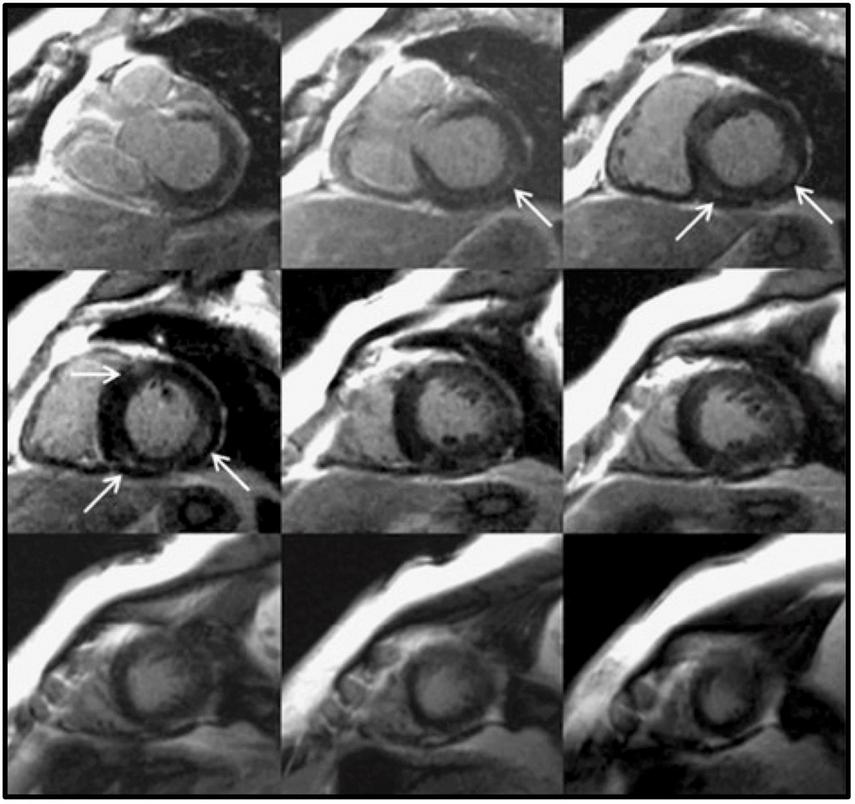

FIGURE 2

Focal myocardial fibrosis in a hypertensive patient. Late gadolinium enhancement in a 63-year-old female patient with longstanding hypertension. The arrows show an area of intramyocardial late gadolinium enhancement in the basal and mid inferoseptal and inferolateral segments. This is not the most typical fibrosis pattern in hypertension, which is usually diffuse. Adapted from Maceira et al. with permission (36).